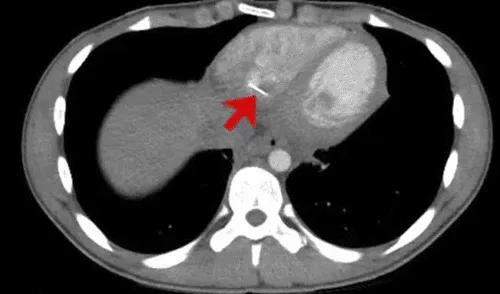

Los resultados obtenidos no resolvieron el misterio del dolor, por lo que decidieron realizar una tomografía computarizada donde finalmente se reveló que en la parte inferior derecha de su corazón tenía alojado un objeto metálico punzante.

Después de ello, los médicos entrevistaron al joven, este dijo que no había ingerido ningún objeto extraño ni había experimentado un trauma físico en el pecho. Pero, en una conversación posterior, comentó que solía adaptar su ropa él mismo, por lo que a veces llevaba alfileres en su boca.